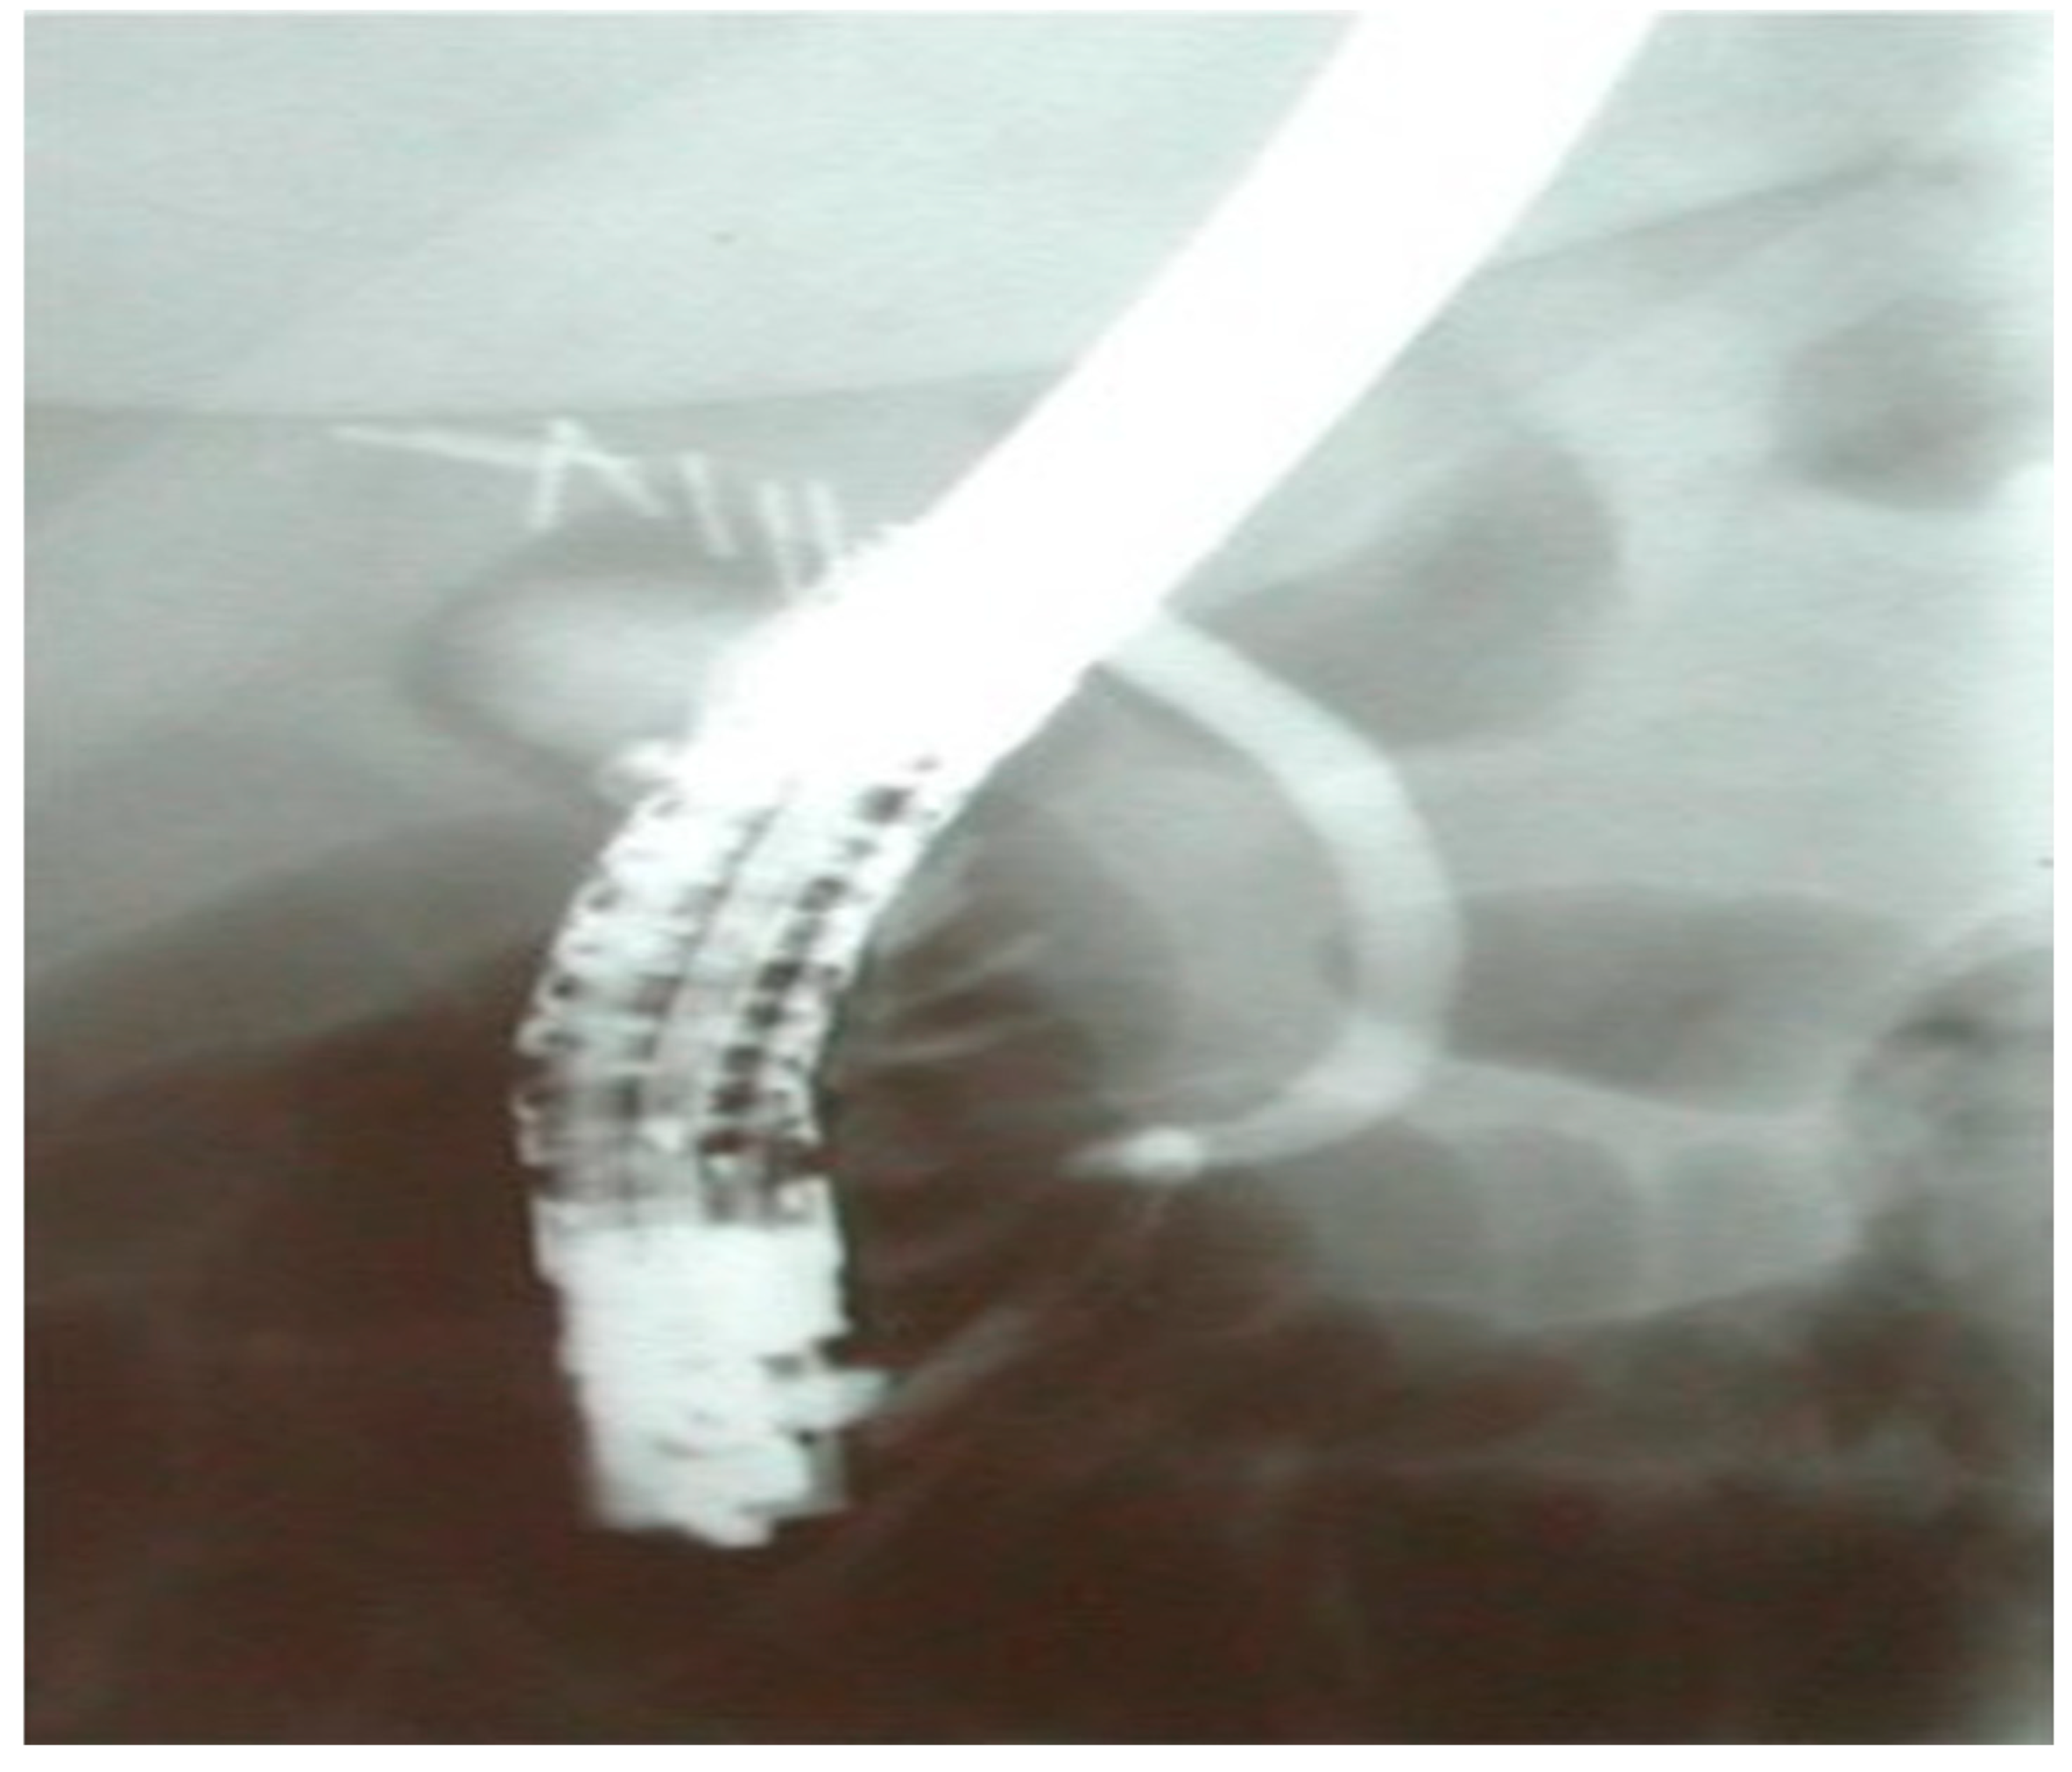

In Figure 2, a completely dissected common bile duct is presented. The cholangiographic image was obtained from a 37-year old female patient who presented with a bile leak post-laparoscopic cholecystectomy and was submitted to endoscopic retrograde cholangiopancreatography in our department.

Figure 2. A completely dissected CBD post-cholecystectomy.